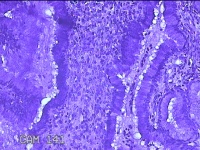

宫颈2点、10点组织

性别

女

年龄

21岁

临床诊断

人乳头瘤病毒感染

一般病史

发现人乳头瘤病毒5个月。

标本名称

大体所见

1.“宫颈2点组织”:灰白粉红色组织0.8x0.5x0.2cm一块。 2.“宫颈10点组织”:灰白暗红色组织0.8x0.6x0.3cm一块。